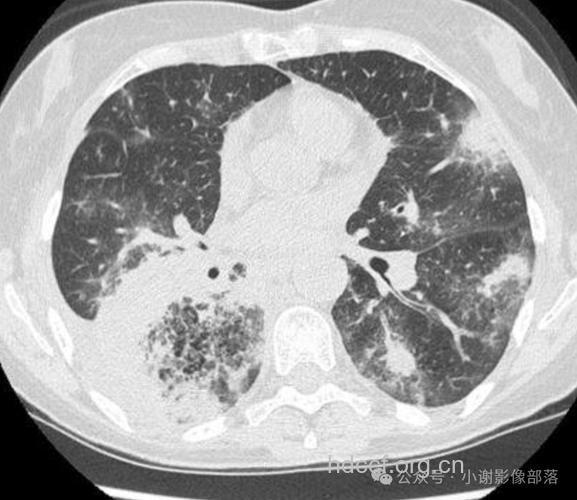

2、弥漫性肺癌内部表示为肿瘤密度较匀称,部门密度不均,可见小泡征、支气管充气征以及蜂窝状转变,病理上为未被肿瘤加害的肺构造,小支气管或细支气管的断面,以及棘状突起之间的气腔。

3、边沿多不规则,凸凹不平,见分叶征,多为深分叶,这是因为肿瘤发育历程中瘤体各部位所受阻力纷歧致,发展速率不均而形成的。弥漫性肺癌分叶形成的首要病理根本是小叶间内的纤维增生所致。可见锯齿征,小棘状突起与细毛刺,弥漫性肺癌的毛刺多细短,较麋集,呈放射状,近瘤体处略粗。病理上为肿瘤的四周浸润及间质反响所致。这也是常见的弥漫性肺癌的症状。